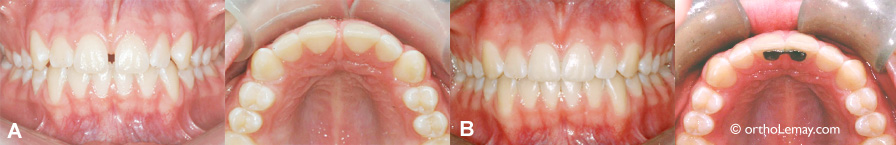

(A) Bonne occlusion générale mais présence d’un espace important entre les centrales supérieures.

(B) Après la fermeture de l’espace, une attelle de rétention est posée sur la face interne pour prévenir la ré-ouverture de l’espace en stabilisant les dents.

(A) Avant les corrections; présence d’un espace de 3,5 mm entre les centrales supérieures.

(B) Après la fermeture du diastème.